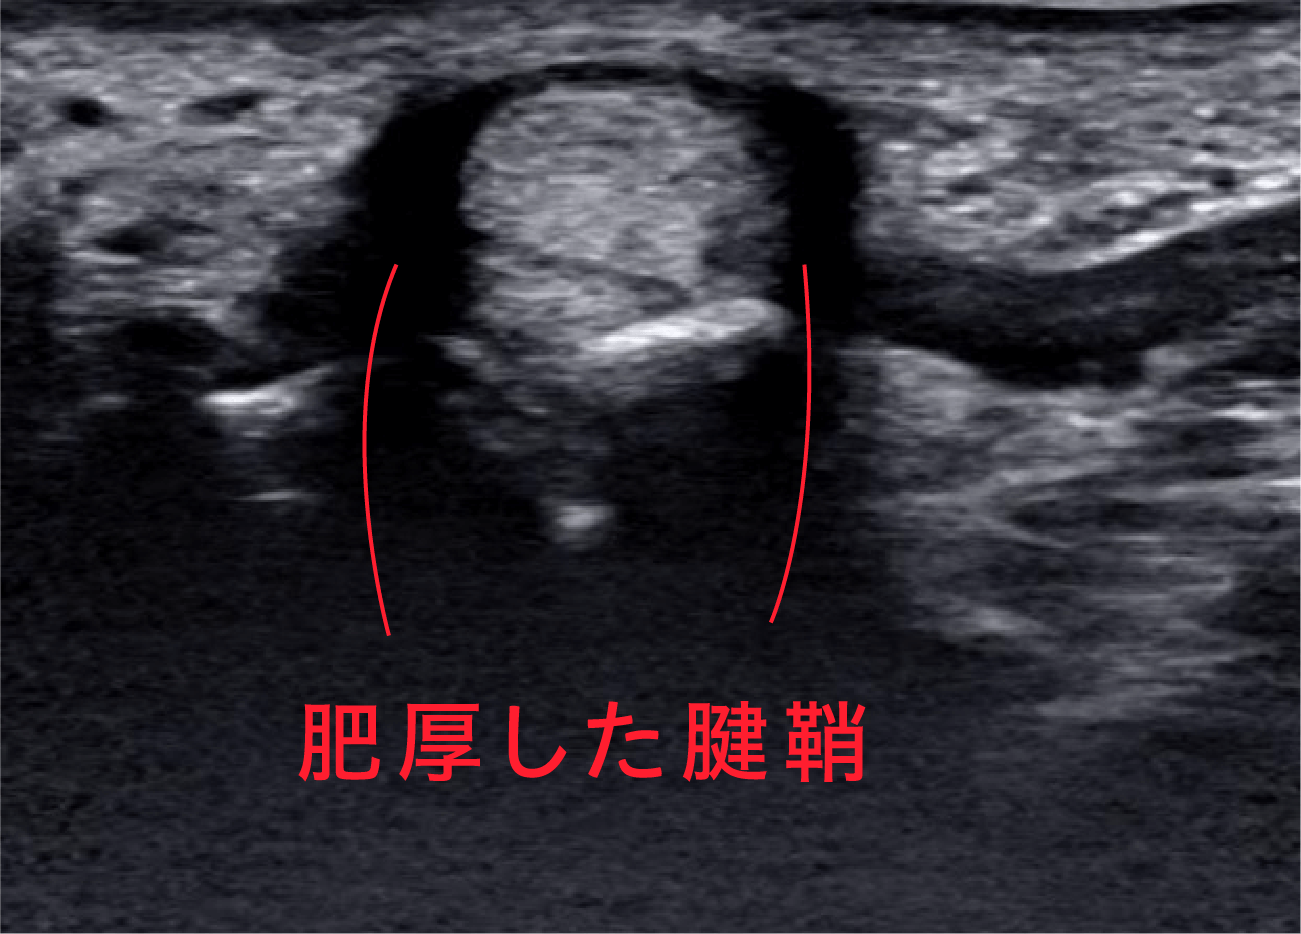

パンパンに腫れた腱鞘が確認できます。